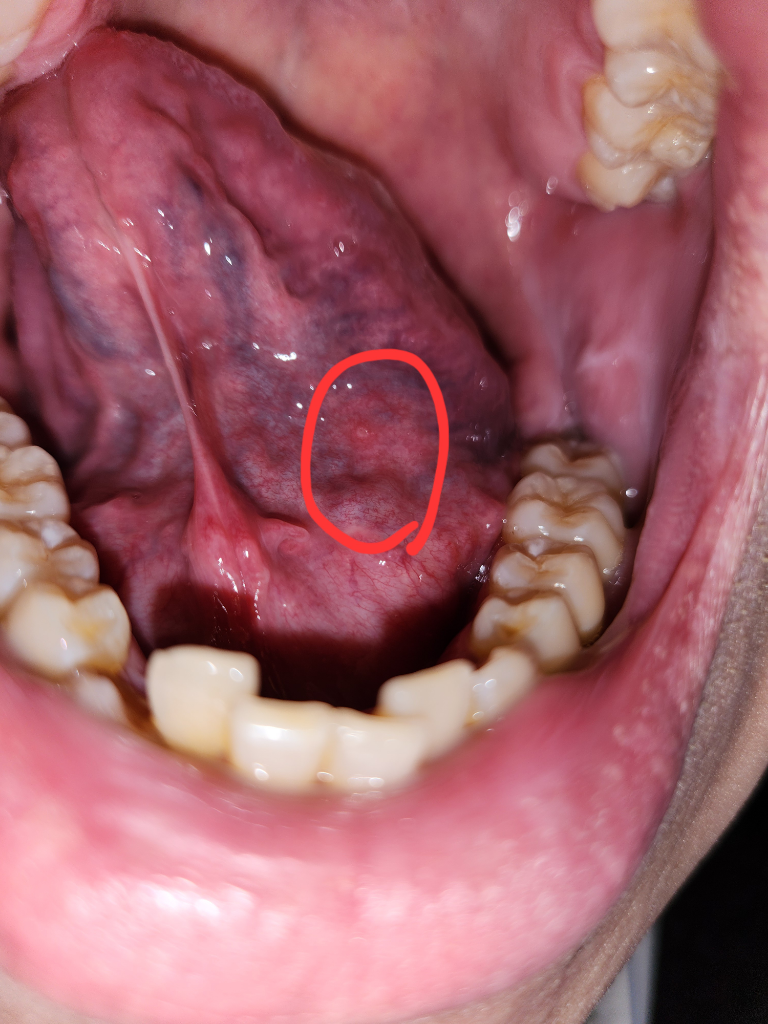

안녕하세요. 김지훈 치과의사입니다.

단순 구내염일 가능성이 높지만 지켜보시고 크기가 더 커지거나하면 치과를 가보시는게 좋겠습니다

안녕하세요. 최석민 치과의사입니다.

해당 부위 병소는 구내염이 맞는 것 같습니다 특별한 증상이 없거나 약간의 통증이 있을 수 있는데 1~2주면 괜찮아집니다

혀밑에 일종의 구내염처럼 물집이 잡힌것 같습니다. 시간이 지나면 괜찮아 질꺼 같으니 너무 걱정은 안하셔도 될것같습니다.